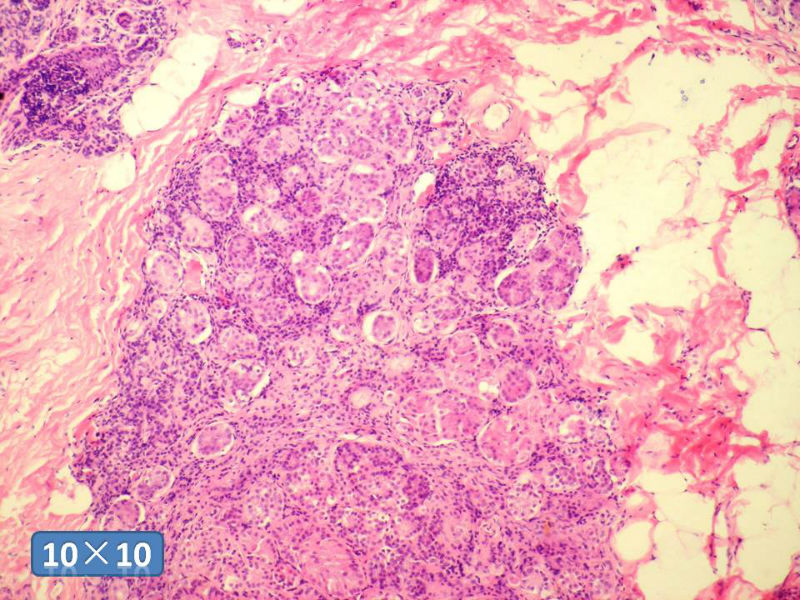

女性,50岁,乳腺肿物,冰冻切片(图1-25)

HE

DCIS LCIS IDC